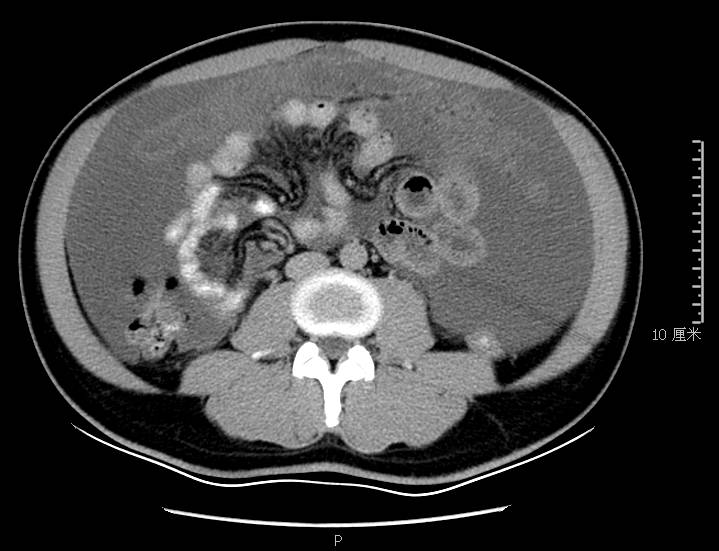

全腹CT:(1)结合病史考虑腹膜炎(见图2A),大量腹水;(2)右骼窝区管状样结构,考虑阑尾扩张(见图2B);(3)肝脏多发小囊肿(见图2C);(4)肝内胆管轻度扩张,建议隔期复查。

图2a大网膜成饼状(CT腹腔横断图象上出现肠曲被前面及两侧的肿瘤策划限制在中央

本例确诊后对B超及CT再次回忆发现:腹腔、盆腔可见不均质中强回声包块,部分呈囊实状,腹膜增厚,大网膜成饼状(如图2A)和肝周可见不均质中强回声弧形压迹、脾周可见不均质中强回声包饶,肝脏成扇贝样改变(如图2C),但在诊断报告中未提及。有学者发现mantle和scalloping(如图2A,2C)在PMP中具有代表性,且mantle较scalloping更为常见,若mantel征同时伴有大小不一的囊性改变,则更具诊断价值。

通过本病例分析认为此类患者,腹穿时若发现腹水不易抽出或抽出物为黏稠胶冻样,腹部B超提示液性暗区内有漂浮的团状回声有分隔,撞击腹部后可出现“礼花”样改变,肝脾包膜完整不光滑,有弧形压迹,全腹部CT示弥散占位,可见mantle和scallping征、大网膜成饼状且阑尾扩张应高度怀疑本病。